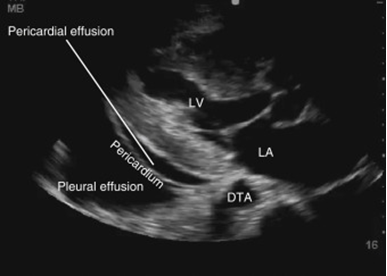

Briefly highlighting some unseen evidence of two comorbid COVID-19 patients

Abdullah, Muhammad Salman, Sher Ali, Riaz Muhammad, Aiman Waheed, Muddasir Khan, Sana Ullah, Carlos Augusto Fernandes de Oliveira